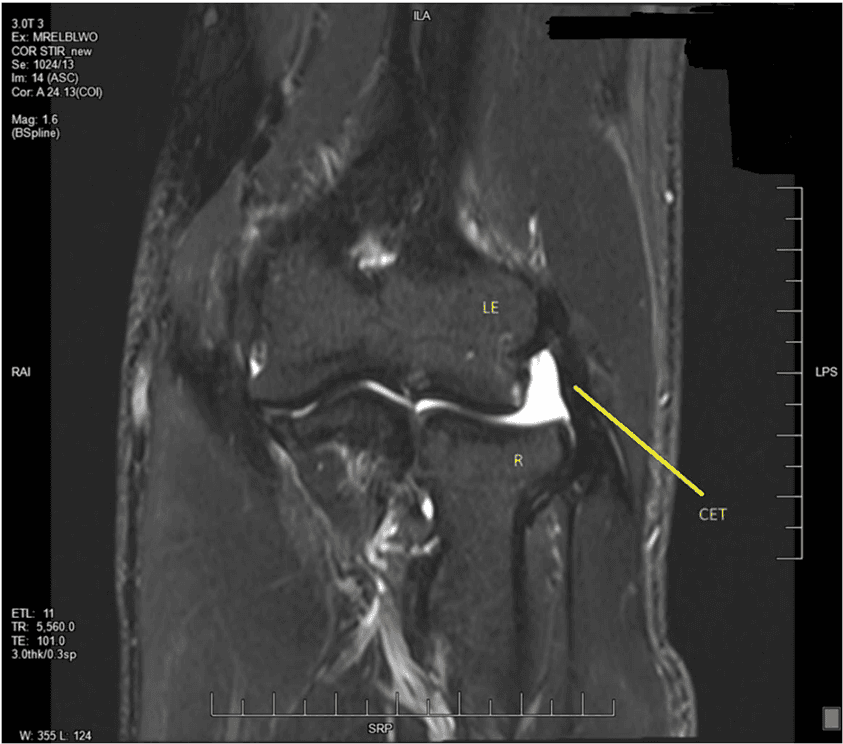

Regeneration of full thickness common extensor tendon tear after percutaneous microfragmented adipose graft

Imran J Siddiqui, Alyssa Ritner, Sanjay Mahadevan, Kyle J Dineen, Roosevelt Desronvilles, Regenerative Medicine, 2024